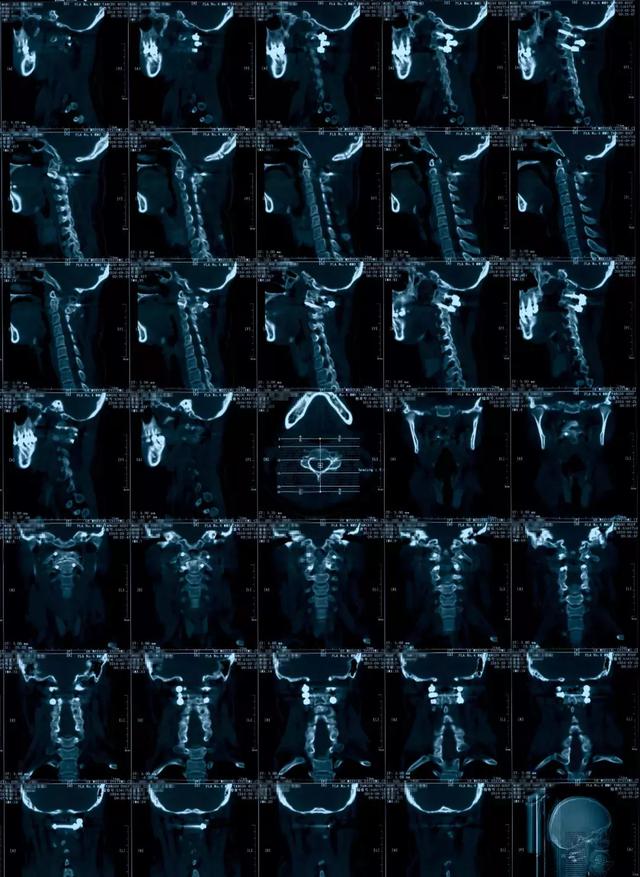

寰枢椎脱位ct

寰枢椎半脱位

寰枢关节脱位的影像诊断

寰枢椎脱位

寰枢关节半脱位的影像学诊断

寰枢椎半脱位(dr)

病例寰枢关节半脱位该如何诊断与治疗

寰枢关节脱位

卧位旋牵法治疗儿童寰枢关节半脱位临床报告1例(现己5例)

病例点评寰枢椎脱位1例

难复性寰枢椎脱位

一例寰枢关节半脱位

一例寰枢关节半脱位的病例报道(转自网络)